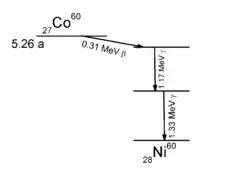

En 1938, John Livingood et Glenn Seaborg découvrent le cobalt 60.

La cobaltothérapie désigne l'emploi des rayonnements du cobalt 60 en thérapie du cancer.

Le cobalt est un élément monoisotopique et mononucléidique : il n'existe à l'état naturel que sous la forme d'un seul isotope, isotope stable, 59Co. On lui attribue une masse atomique standard de 58,933195(5) u. Cependant, 28 radioisotopes artificiels ont été caractérisés, le plus « stable » étant le 60Co avec une demi-vie 5,2714 ans, suivi de 57Co avec une demi-vie de 271,79 jours, de 56Co (77,27 jours) et 58Co (70,86 jours). Tous les autres isotopes ont une demi-vie inférieure à 18 heures et pour la majorité d'entre eux inférieure à une seconde. Le cobalt possède également 11 isomères nucléaires, tous ayant une demi-vie inférieure à 15 minutes.

Cobalt 60 (isotope radioactif)

Le cobalt 60 a de nombreuses utilisations comme source de rayons gamma γ, en raison de sa demi-vie relativement courte (5,27 ans), donc plus facile à éliminer en comparaison d'autres isotopes émetteurs de telles particules. On retrouve ainsi les « bombes au cobalt 60 », sources de rayons γ de 1,17 et 1,33 MeV :

- en radiothérapie des unités de médecine spécialisées en cancérologie, où elles ont remplacé les techniques au radium mises au point par Marie Curie ;

- dans le traitement par radiation de la nourriture pour sa stérilisation ;

- dans le contrôle industriel des matériaux par radiographie pour repérer les défauts des pièces.

Toutefois, le cobalt 60 de synthèse (produit par exposition de cobalt « naturel », l'isotope 59, aux rayonnements neutroniques d'un réacteur nucléaire) n'est pas totalement pur, et contient toujours d'autres isotopes radioactifs à désintégration ε (epsilon), émetteurs de rayonnement gamma dangereux[e] car ce rayonnement hautement énergétique détruit les noyaux et les contamine en éléments radioactifs persistants.

De plus l'enrichissement et la purification du cobalt 60 nécessitent des techniques de centrifugation similaires à celles utilisées pour l'enrichissement des isotopes à usage militaire, techniques hautement surveillées car stratégiques sur le plan international.

Aussi, on préfère maintenant utiliser des accélérateurs d'électrons, semblables aux tubes cathodiques de nos moniteurs et téléviseurs mais à des niveaux d'accélération bien supérieurs, qui produisent des flux plus purs et mieux contrôlés de particules bêta. Mais leur utilisation nécessite un équipement beaucoup plus lourd qu'une simple capsule de cobalt 60. Cette méthode est de ce fait principalement utilisée en milieu industriel, et aujourd'hui aussi en milieu médical.